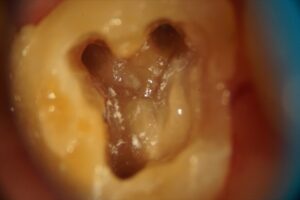

顕微鏡根管治療症例

HOME › 顕微鏡根管治療症例

症例一覧